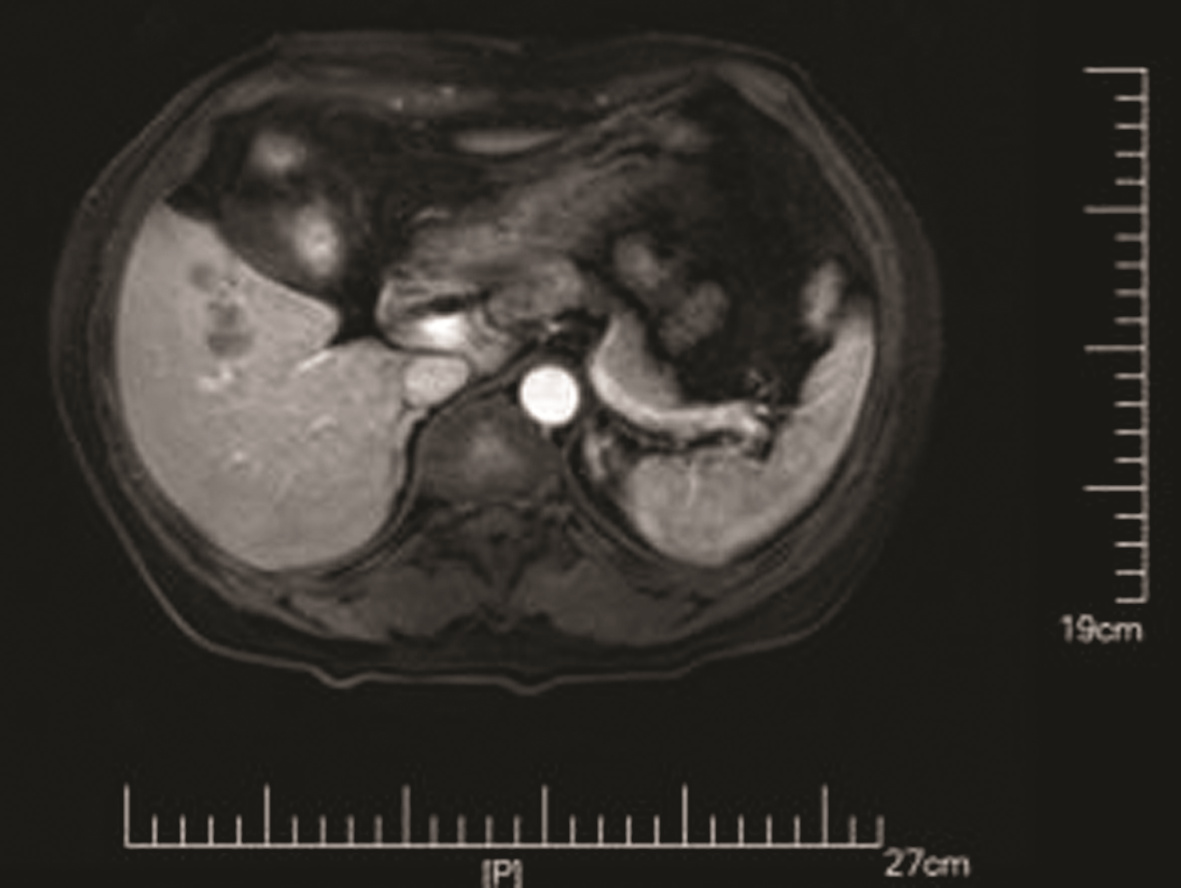

乙型肝炎肝硬化上消化道出血的ΔCT特征性表现及预测模型的建立

李俊杰, 孙岩岩, 李将宏, 郑虹

2022, 38(5): 1081-1085. DOI: 10.3969/j.issn.1001-5256.2022.05.020

摘要(1053) HTML (308) PDF (2671KB)(64)

摘要:

目的  本研究旨在寻找乙型肝炎肝硬化CT特征,建立肝硬化上消化道出血预测模型,预测出血风险。  方法  回顾性分析2015年1月—2021年6月天津市第一中心医院101例型肝炎肝硬化患者的数据,将其分为上消化道出血组(P=58)及非出血组(n=43)。比较两组间实验室检查以及强化CT检查测的平扫期、动脉期、门脉期以及静脉期的CT值,并计算各期间CT值的变化(ΔCT)。计量资料两组间的比较使用t检验或Mann-Whitney U检验;使用logistic回归分析方法,预测相关危险因素;通过计算受试者工作特征曲线下的面积评估模型辨别力,而模型校准则通过Hosmer-Lemeshow确定。在多变量logistic回归分析结果的基础上,使用Rstudio4.1.2软件的R包构建预测的列线图模型,并绘制相应的ROC曲线、校准曲线以及临床决策曲线。  结果  非出血组血清TBil、WBC、PLT水平与出血组比较,差异均有统计学意义(P值均<0.05);两组在肝-Plain、脾-P-Plain、脾-P-A ΔCT值存在统计学差异(P值均<0.05)。单因素logistic分析结果显示,白细胞(OR=0.770,95%CI:0.624~0952, P=0.016)、血小板(OR=0.979,95%CI:0.965~0.994, P=0.006)、肝脏平扫期(OR=1.142,95%CI:1.058~1.233, P=0.001)、脾脏门脉期-平扫ΔCT值(OR=0.979,95%CI:0.959~1.000, P=0.050)、脾脏门脉期-动脉期ΔCT值(OR=0.979,95%CI:0.944~0.994, P=0.015)在乙型肝炎肝硬化患者发生上消化道出血与未出血两者之间差异具有统计学意义。多因素logistic分析结果显示血小板(OR=0.968,95%CI:0.944~0.993, P=0.011)、肝脏平扫期(OR=1.148,95%CI:1.047~1.259, P=0.003)、脾脏门脉期-动脉期ΔCT值(OR=0.951,95%CI:0.908~0.995, P=0.030)为上消化道出血的独立危险因素。基于多因素logistic分析结果,构建了乙型肝炎肝硬化上消化道出血的预测模型并绘制校准曲线。该模型的受试者特征曲线下面积为0.801,cut-off值为0.433,其对应的敏感度是81.4%,特异度是77.6%。模型的校准曲线与理想曲线贴合良好。  结论  乙型肝炎肝硬化肝脏具有特殊的ΔCT变化,通过ΔCT构建的预测模型对于乙型肝炎肝硬化上消化道出血具有良好的预测能力。